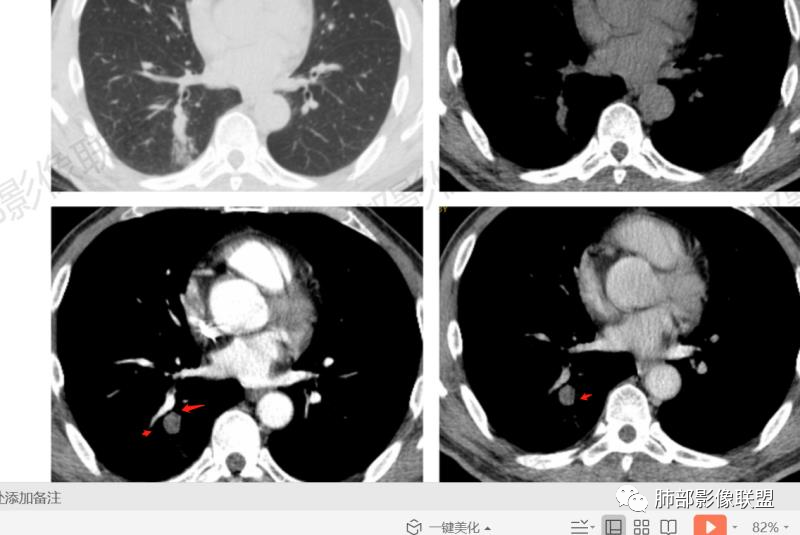

第一次CT:右肺下叶实性结节,近段血管束增粗并与结节相连,结节边缘光滑,密度均匀。第二次(间隔九天,治疗后复查):结节增大,伴有磨玻璃,边界欠清,远端树丫,结节内可见空泡影,壁光滑,临床无明显症状,短期增大先考虑非肿瘤性病变,炎性假瘤,结核,隐球菌。

中年男性患者,1年前发现肺结节,7天前复查结节较前增大,有糖尿病且控制不佳,胸部CT:右肺下叶后段类圆形结节病灶,边界清楚,内部密度均匀,治疗后见内壁光滑的小空洞,结节远端有阻塞性炎症,考虑炎性病变,结核可能,鉴别鳞癌。

右肺结节,气管堵塞,结节边缘光滑,密度均匀,远端斑片影。治疗后复查结节增大,空洞,斑片影伴有磨玻璃,边界欠清,糖尿病,短期增大,考虑结核,隐球菌。

男性病人48岁,既往有糖尿病的病史,影像学表现,右肺下叶后段类圆形的小结节病灶 ,边界比较光整,内见小空洞影 ,病灶远端见小片状的渗出性病灶,增强扫描病灶轻度的强化。病灶在治疗的过程中短期内有增大。整体病灶表现为一个光整结节+远端阻塞性肺炎+小空洞+轻强化,周围无卫星病灶,考虑感染性病变,隐球菌感染?结核次考虑。

右肺下叶结节,边缘光整,密度均匀,伴阻塞炎症,增强无强化,抗感染一周复查效果差,结节内小空洞,阻塞明显,胸膜增厚,糖尿病病史,首先考虑结核,隐球菌待排

糖尿病病史,右肺下叶结节,边缘光整,密度欠均匀,远端阻塞炎症,增强强化不明显,抗感染一周复查,结节较前增大,内出现小空洞,阻塞明显,胸膜增厚,首先考虑结核,隐球菌待排。

中年男性,糖尿病史,无症状。右肺下叶类圆形结节,边缘光滑,支气管近端阻塞,远端淡片影,树芽还是阻塞性炎症?感觉像树芽,沿支气管分布,无明显强化,治疗一周后复查CT,支气管通而不畅,近端小空洞,远端淡片影加重。考虑肺结核可能性大,鉴别肺癌并阻塞性肺炎。

中年男性,糖尿病史,无症状。右肺下叶类圆形结节,边缘光滑,远端树芽征,沿支气管分布,无明显强化,治疗一周后复查CT,支气管通而不畅,近端小空洞,远端树芽征进展为磨玻璃影。考虑肺结核可能性大。

中年男性患者,有糖尿病基础。右下肺结节较1年前增大,CT表现:右肺下叶后段类圆形结节,边界清楚,边缘部分膀隆、部分平直,内部大部分密度均匀,其中见小条状低密度影(粘液栓?),近端支气管堵塞(抗感染治疗后见大部分通畅,近端支气管进入截断入口圆钝、远端支气管稍扩张),综合考虑结核可能性大,治疗后病灶呈支气管挂果,注意鉴别错构瘤。

2.右肺下叶背段指尖大小结节影伴外围片状影及小结节影,片影中有结节感。

3.近背段支气管开口附近结节密度不甚均匀,未见钙化或脂质密度区。边界清楚光整,内侧平直,未见典型深分叶及毛刺,增强扫描轻度强化。

4.哌拉西林、左氧氟沙星等治疗一周后,较大结节影及外围病灶范围均见增大。

5.背段支气管于结节内侧份“旁现侧出”,管壁完整,管腔少量分泌物,近乎疏通状态。结节内隐约出现微小含气空腔。

6.肺门及纵隔未见增大淋巴结。